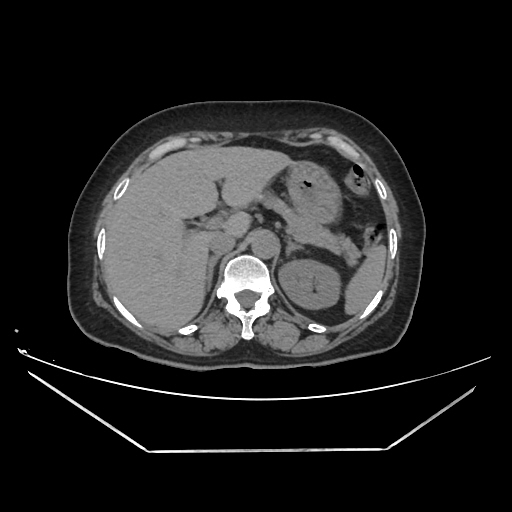

A CT abdomen revealed a left adrenal cortical tumor.

Her abdominal X-ray also reveals a right renal stone although she never complained of renal colic.

CT images: